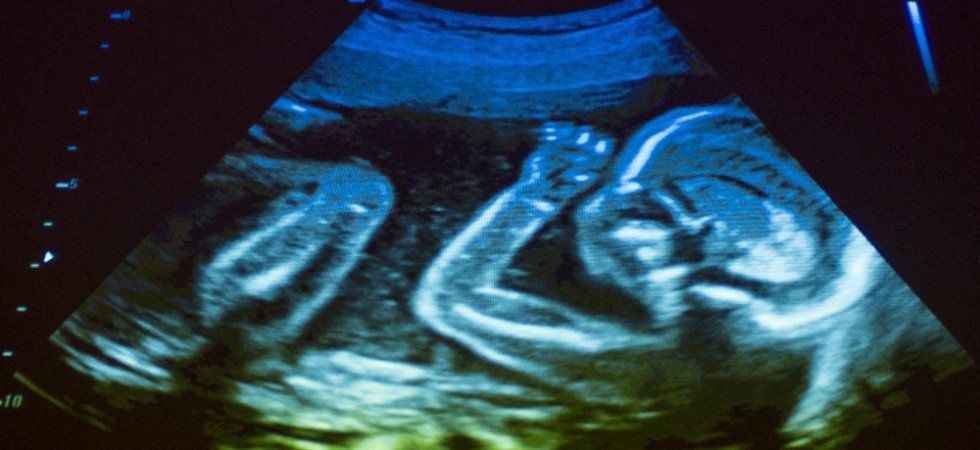

La plus haute juridiction française a confirmé la condamnation d’une échographiste pour ne pas avoir décelé une anomalie chromosomique durant la grossesse, entraînant une indemnisation substantielle au profit des parents.

La Cour de cassation a définitivement validé la condamnation d’une praticienne spécialisée en échographie, reconnue responsable de n’avoir pas identifié la trisomie 21 lors du suivi de grossesse d’un couple. Cette omission a empêché les parents d’exercer leur droit à une interruption médicale de grossesse. Ce n’est qu’à la naissance que le diagnostic a été établi, les contraignant à réorganiser entièrement leur vie professionnelle et familiale.

L’échographiste avait contesté le montant des réparations allouées aux parents. La Cour a néanmoins confirmé le versement de 300 000 euros au titre du préjudice subi, incluant la perte de chance et les conséquences économiques durables. Cette décision souligne l’obligation de moyens qui incombe aux professionnels de santé dans le cadre du diagnostic prénatal, et la portée des indemnités en cas de manquement.